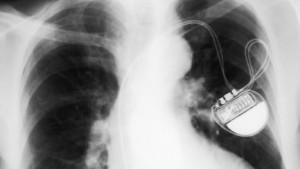

Whilst the means in which a pacemaker interacts with the body’s physiology is complex, the mechanical process behind it is relatively simple. Basically, pacemaker cells produce and deliver highly-systematic electrical pulses to heart muscle cells so they can function rhythmically, within consistent and repetitive patterns. The signal that they produce is known as the sinus rhythm and can sometimes be disrupted fairly easily by a variety of factors such as stress, anxiety and excessive alcohol-use.  A healthy sinus rhythm ensures that blood is pumped around the body efficiently, and that oxygen-levels in the blood are sufficient. Therefore, if a pacemaker fails, the only option is often for it to be replaced – but this can only be done if the patient is healthy enough to survive the trauma of surgery.

Fortunately, single genes can be inserted into the body simply and quickly, and are considered to be a safer alternative to the insertion of stem cells, which carries the risk of the onset of cancer in the patient. Whilst, there is still much research to be conducted on the subject, the effectiveness of the procedure is good news for the millions of people who have to undergo hazardous surgery each year, in order for pacemakers to be inserted.